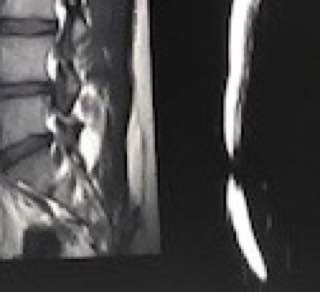

An intriguing case involved severe herniation and disc rupture between L4 and L5 vertebrae, causing intense pain. Opting out of surgery, the patient chose to try Discogel. Due to severe foraminal stenosis from the extruded disc, the Discogel injection was cautiously prolonged to one hour. Post-injection CT scan revealed effective penetration into fragmented disc components in the narrowed foraminal space.

The patient's pain gradually diminished after 4-5 weeks, and complete relief was achieved after several months.

The first image is six months post-injection, and the second image is three years post-injection."

Important Note: Foraminal disc herniation and migration into the intervertebral foramen significantly reduce the likelihood of a favorable response to Discogel injection and are not recommended for such cases.